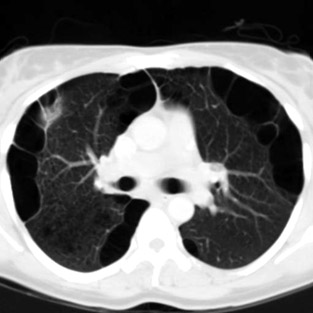

O pneumotórax espontâneo é dividido em primário ou secundário. Os primários são causados por rompimentos de blebs, que são áreas de fraqueza da parede pulmonar onde acredita-se que sejam causadas pelo crescimento rápido do órgão. Estas se localizam geralmente no ápice dos pulmões e são mais frequentes em pessoas do biotipo longilíneo (magras e altas). Geralmente ocorre em pacientes jovens e tem frequência pouco maior em tabagistas.

Os secundários são gerados por rompimento de bolhas pulmonares, também áreas de fraqueza das paredes, causadas por doenças pulmonares subjacentes. A mais frequente, responsável por mais de 90% dos casos é o DPOC (doença pulmonar obstrutiva crônica) causada pelo tabagismo. Outras causas são esclerodermia, tuberculose, fibrose cística, entre outras.